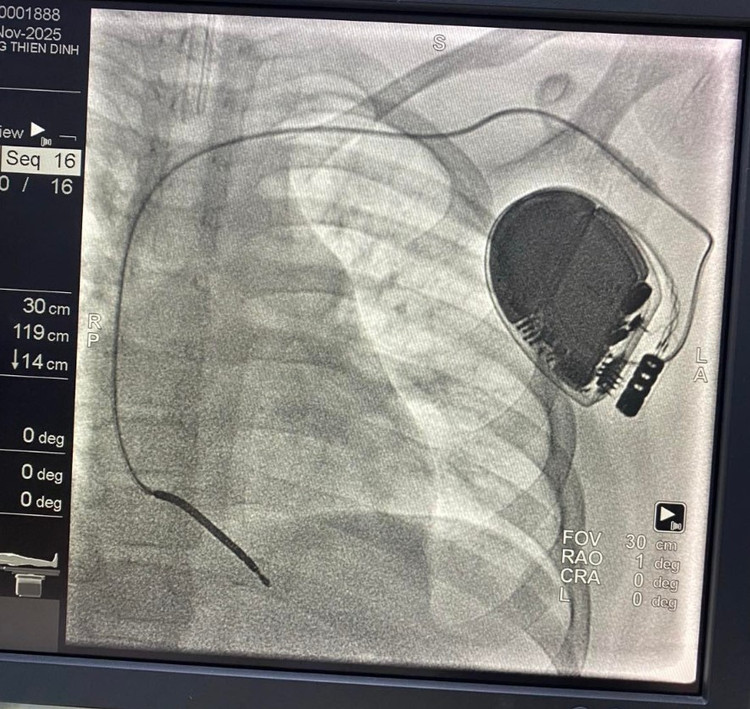

Tại Bệnh viện Nhi Đồng Thành Phố, Trung tâm Tim mạch đã quyết định cấy máy khử rung tim tự động (ICD) cho bé – một thiết bị có khả năng phát hiện và sốc điện ngay lập tức khi xuất hiện cơn nhịp nhanh thất nguy hiểm, ngăn chặn đột tử.

Đây là ca đầu tiên được triển khai tại bệnh viện, cũng là lần đầu ê-kíp thực hiện kỹ thuật tạo đường mổ dưới nách để cấy máy – phối hợp cùng đồng nghiệp phẫu thuật nhằm đảm bảo tính thẩm mỹ tối ưu, tránh để lại sẹo trước ngực như cách làm truyền thống.

ngung-tim-2.jpg

ngung-tim-3.jpg

Máy khử rung tim tự động trong lồng ngực trẻ sau can thiệp trên phim chụp - Ảnh BVCC